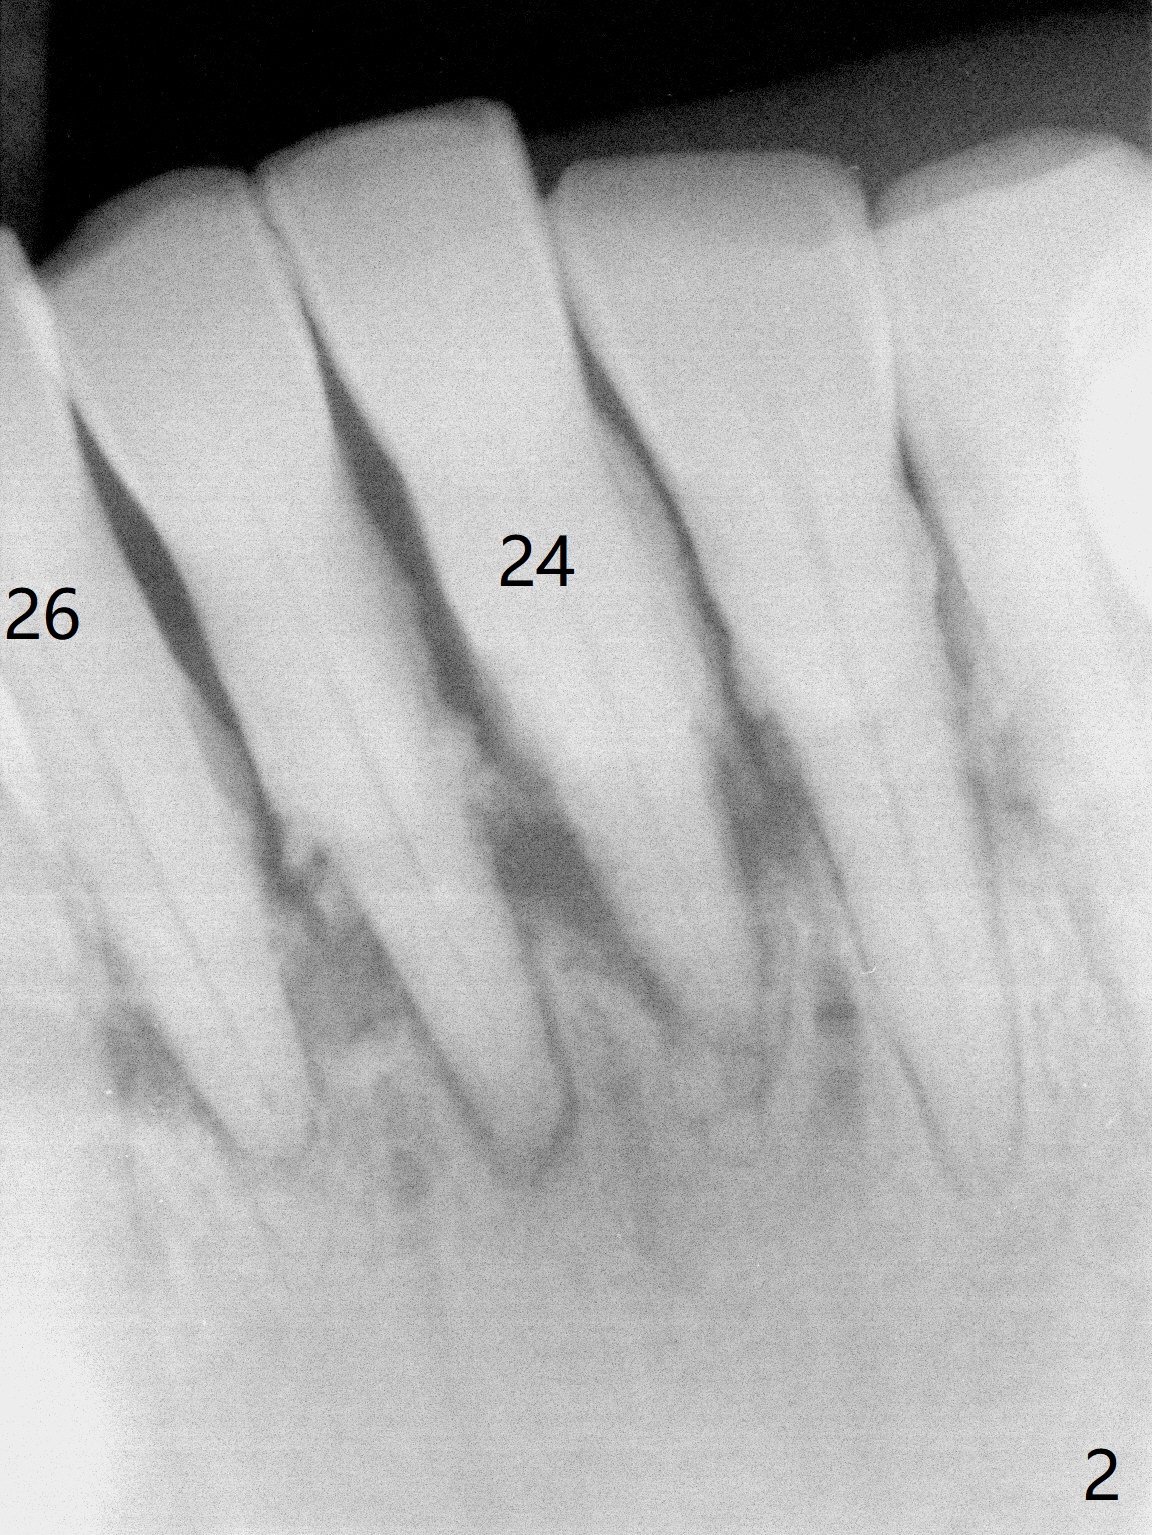

A 73-year-old man has poor dentition with lack of posterior support (Fig.1). The teeth #24-26 were mobile > 1 year ago (Fig.2), while the tooth #27 is reportedly now. To counter heavy mastication, long implants are to be placed (Fig.3). Take preop photos and PAs.